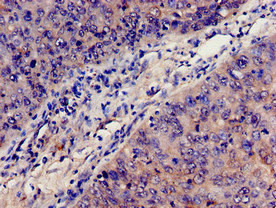

Immunohistochemistry analysis of human colon cancer using CSB-PA10599A0Rb at dilution of 1:100